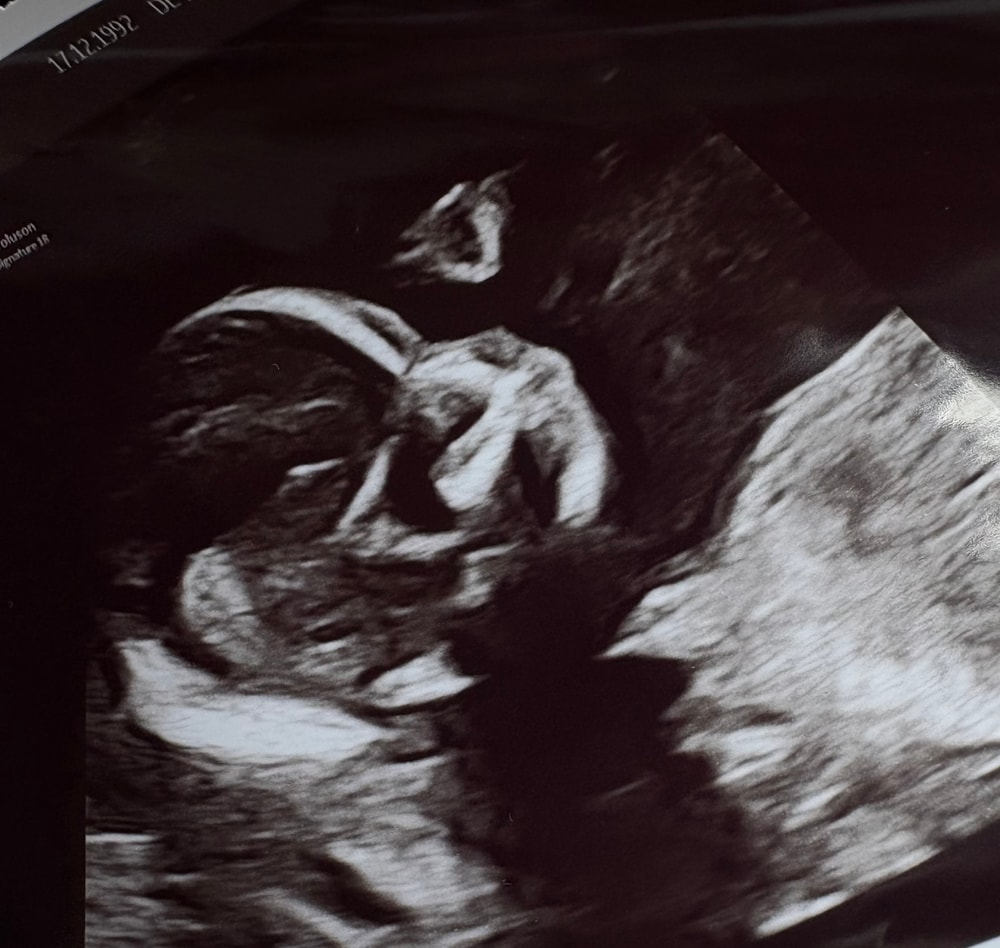

4 месяца ♥️

сходила сейчас к акушерке, она решила с малышом поздороваться. Пол не показал свой 🙈🫠